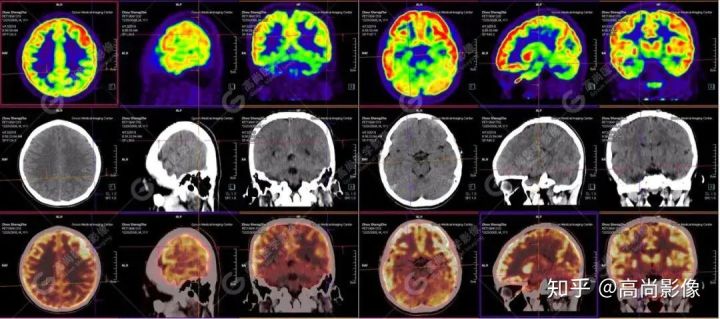

【高尚影像】【病例】PET/CT在癲癇病灶定位診斷中的應(yīng)用

【病史摘要】男性,11歲;9歲時(shí)無(wú)明顯誘因癲癇發(fā)作,發(fā)作時(shí)雙眼上翻,意識(shí)不清,全身抽搐,每年發(fā)作4~5次,近期未行腦電圖及MRI檢查。

【PET/CT 】

提示: 大腦左側(cè)頂葉、顳葉(上部)及右側(cè)額葉、枕葉、顳葉(下部)腦皮質(zhì)代謝廣泛減低,尤以右枕葉為著,多考慮與癲癇發(fā)作相關(guān)。